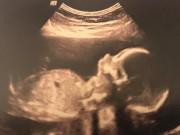

Ngay từ khi còn trong bụng mẹ, các bác sĩ đã nhận định Cherry khó có khả năng sống sót bởi mẹ của bé, cô Nikita đã bị sảy thai tới 4 lần trước đó. Trong khi mang thai Cherry, Nikita còn có triệu chứng suy nhau thai - hiện tượng nhau thai bị thoái hóa, khiến hoạt động tuần hoàn máu và trao đổi oxy giữa người mẹ và em bé bị gián đoạn.

Trước khi chào đời, bác sĩ đã nhận định bé Cherry khó có thể sống sót.